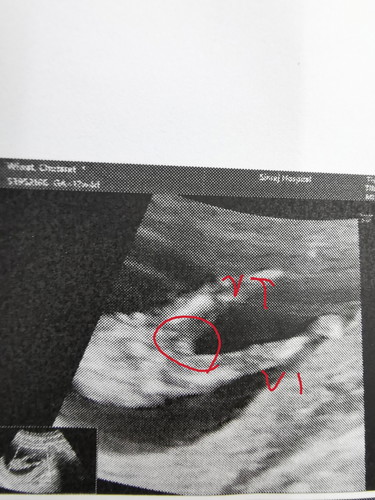

เพศอะไรเอ่ย

แม่ๆคนไหนทราบไหมคะ ว่าเพศอะไร ตอนนี้อายุครรภ์เรา3เดือน ไปตรวจซาวน์นิฟตี้มาหมอยังบอกไม่ได้ว่าเพศอะไรแต่ให้รูปลุ้นมาค่ะ

รอให้อวัยวะเพศโตชัดเจนกว่านี้หน่อยค่ะ 3 เดือน ยังไม่โตชัดค่ะ